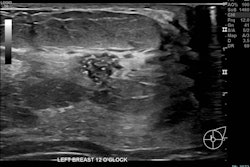

Most current guidelines for mammography screening recommend women start at the age of 50. But younger women may need to screen earlier than that, especially if they are symptomatic, according to review findings presented at the recent annual meeting of the Royal Australian and New Zealand College of Radiologists (RANZCR). Click here for full details.